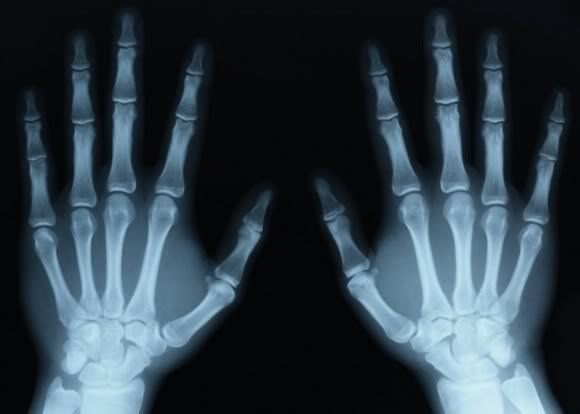

2.3. Chụp X-quang tuổi xương của trẻ

Bác sĩ có thể yêu cầu chụp X-quang bàn tay và cổ tay của trẻ để có thể thấy được các sụn tăng trưởng của xương. Khi còn nhỏ, các sụn tăng trưởng sẽ trở nên mỏng hơn. Đến khi trẻ trưởng thành, những sụn tăng trưởng này sẽ biến mất. Bác sĩ có thể áp dụng nghiên cứu tuổi xương để xác định xem liệu trẻ có thể cao thêm và dài thêm được bao nhiêu nữa.